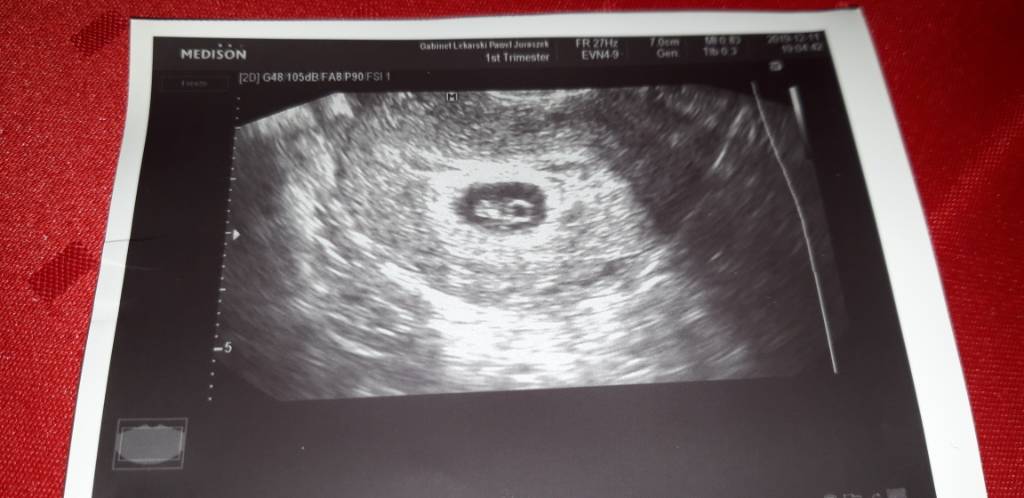

I jest oto moja fasolka [emoji3059][emoji3059][emoji3059]

Pod moim sercem bije malutkie serce coś pięknego marzenia się spełniają

I za każdą z was trzymam mocno kciuki żebyście zobaczyły ten widok

Walczyć trzeba do końca[emoji8]

Jeden minusik tego wszystkiego to ze jest mały krwiak mówi ze to się zdaza ze to moze byc od leków ze sie wchłonie A jak nie to może pojawić się lekkie plamienie

Przepisał mi Duphaston wrazie plamienia i pilny kontakt z nim Zobacz załącznik 1055757Zobacz załącznik 1055758